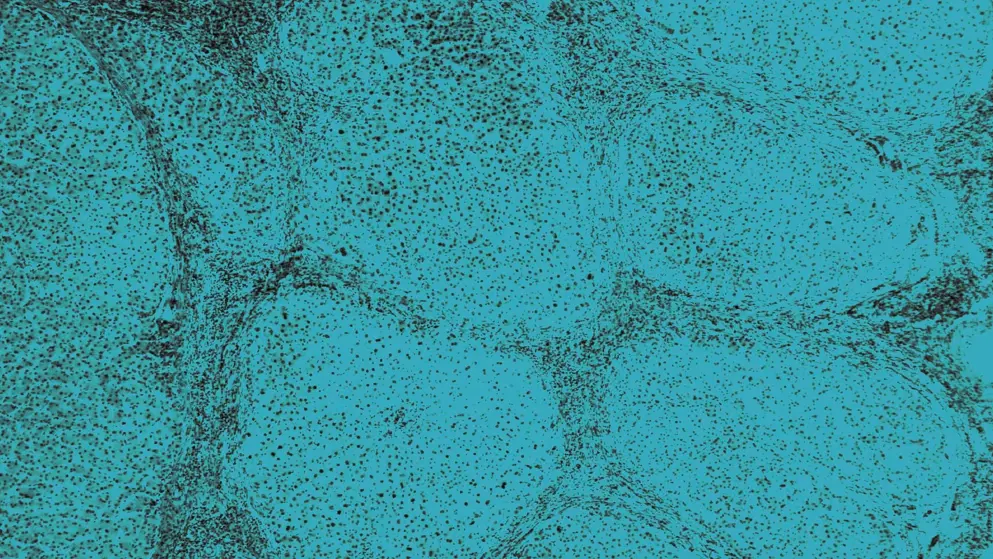

What causes organ damage in AATD?

In AATD, mutations in the SERPINA1 gene result in low or misfolded AAT protein. In the lungs, this allows neutrophil elastase to damage alveolar tissue. In the liver, abnormal AAT accumulates in hepatocytes, causing cellular stress and fibrosis. Clinical presentation varies widely, even among individuals with the same genotype.